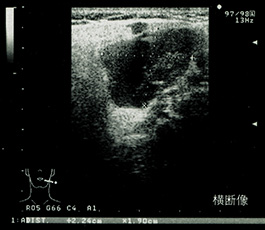

右耳下腺ワルチン腫瘍の横断像。形状は整、境界明瞭、嚢胞形成により輝度の低い不均一な内部エコーを認める。本例は両側の耳下腺に腫瘍を認めた。 |